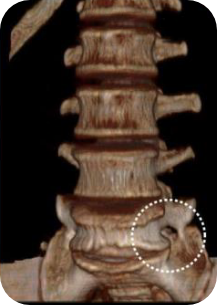

- 극외측협착증

- 척추분리증성 전방전위증